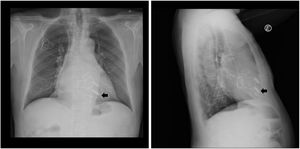

In a post-procedure chest X-ray, both leadless devices are identifiable (Figure 1).